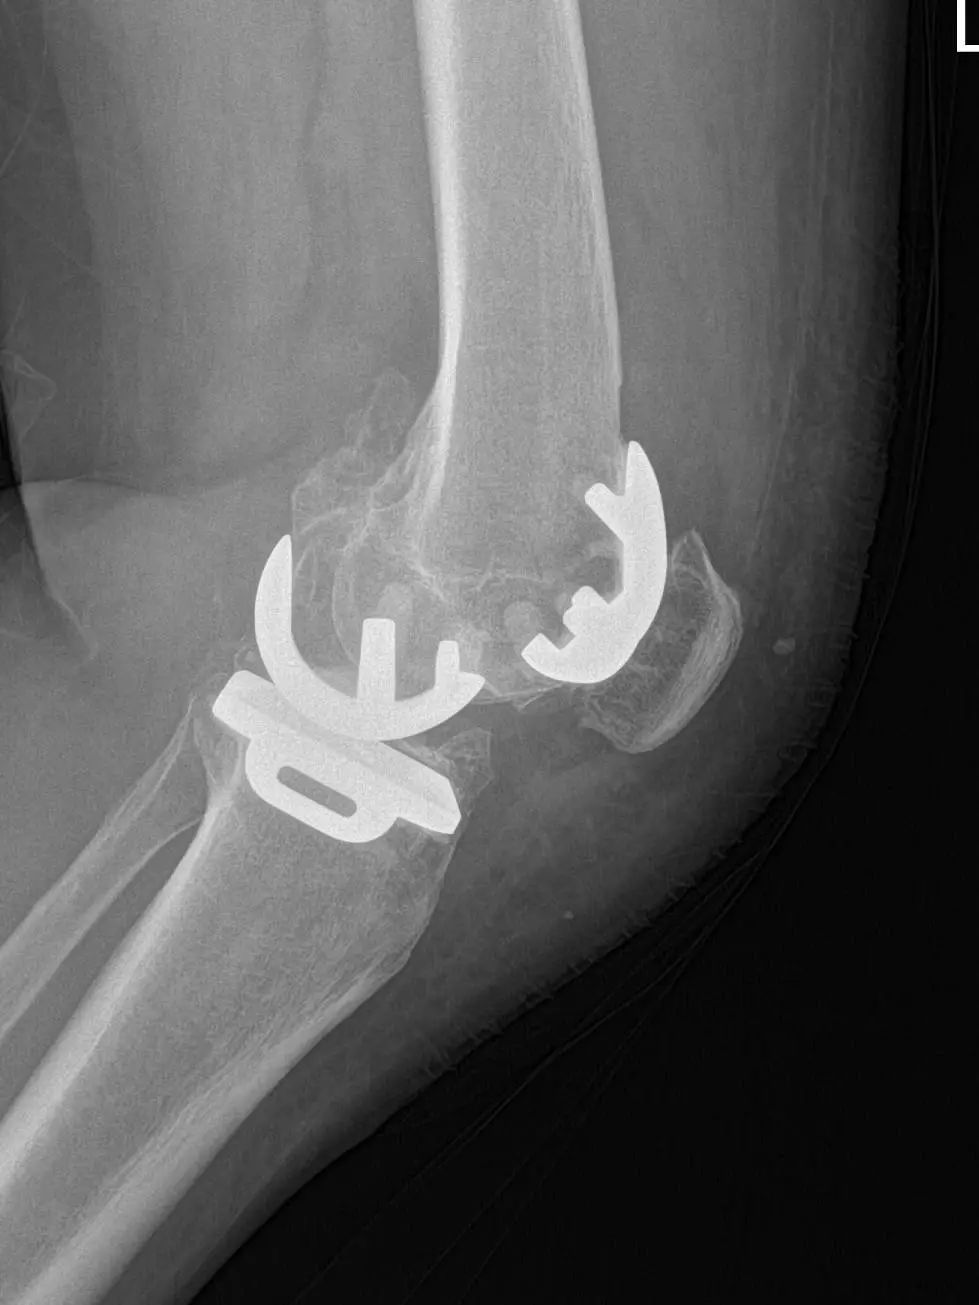

67岁的邵阿姨,双膝关节疼痛10余年,疼痛主要集中在屈伸膝关节时髌骨下。长期口服及外用药物治疗效果欠佳,反复加重,双膝的x线检查提示主要为髌股关节的退行性骨关节炎。程飚主任结合患者症状,影像学结果,体格检查,发现邵阿姨主要问题集中在髌股关节,膝关节间隙,内外侧髁,胫骨平台均可,为解决邵阿姨痛苦,尽可能保留关节,程飚主任决定对邵阿姨进行双侧膝关节的髌股关节表面置换,截骨量较少,邵阿姨第二天就能下地活动了,屈伸关节也不痛了,对手术疗效表示非常的满意。

部分膝关节置换手术目前已是非常成熟的治疗方法,亦属于保膝治疗的一种。主要包括单髁置换,髌股关节置换。单髁置换主要把膝关节内侧髁或者外侧髁表面已经磨损的部分替换成金属的假体和高分子聚乙烯耐磨垫片。髌股关节置换主要把髌股关节表面已经磨损的部分替换成金属的假体。

部分膝关节表面置换局限于膝关节病变部分,尽可能保留剩余健康部分关节,截骨量少,患者恢复快,损伤更小,完全保留了膝关节交叉韧带,本体感受更好。

病变局限于髌股关节的患者,可行髌股关节表面置换;